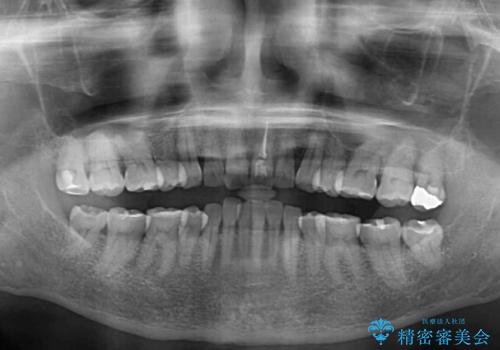

- 上下前歯を中心に、以前行った矯正治療の後戻りが気になるとのことで来院された患者様です。

後戻りは軽度であったため、インビザライン・ライトにて治療を行うこととしました。

矯正治療後は、再度後戻りすることを極力回避するために、下顎前歯の舌側を細いワイヤーを用いて保定することとしました。